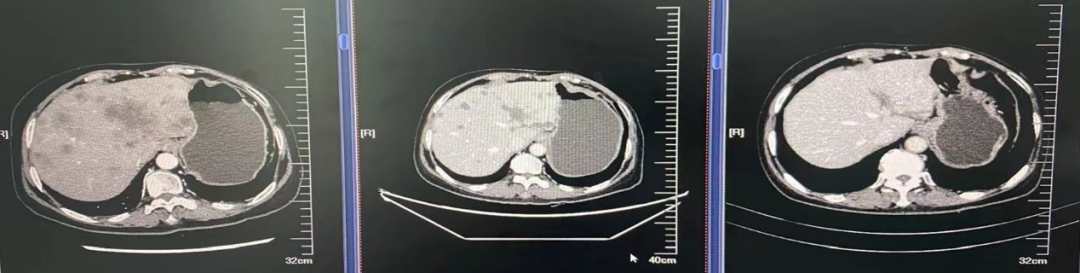

2021.04.05至荥阳市中医院查CT:1、左侧乳腺癌术后;2、双肺多发结节,转移可能,感染性病变待排;3、胸椎异常密度,转移可能;4、冠状动脉钙化;5、肝内多发低密度影。

2021.04.06至河南省肿瘤医院完善CT:双肺、肝、骨多发转移灶可能;ECT:全身多发骨质代谢异常,考虑多发骨转移。